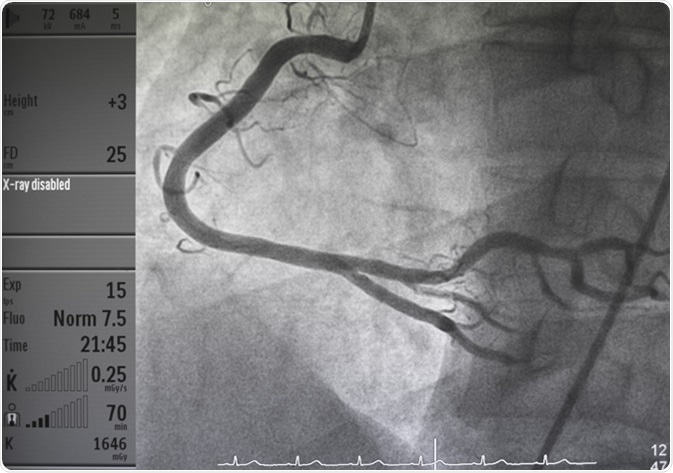

Coronary angiography. Image Credit: Pitchyfoto / Shutterstock

A coronary angiography is used to diagnose blockages in coronary arteries. A special type of contrast material is injected into the blood vessels of the heart, and the x-ray machine is used to track the movement of the dye through coronary arteries. Any blockage or narrowing of the arteries can then be detected through a series of images (angiograms) taken by the x-ray machine.

The contrast material is used to highlight the heart chambers or coronary arteries. The result obtained from an angiography typically demonstrates the numbers of coronary arteries that are either blocked or narrowed down due to atherosclerosis or other factors. It also indicates the exact location and degree of the blockage. In addition, angiograms can provide information on consequences related to previous coronary bypass surgery.